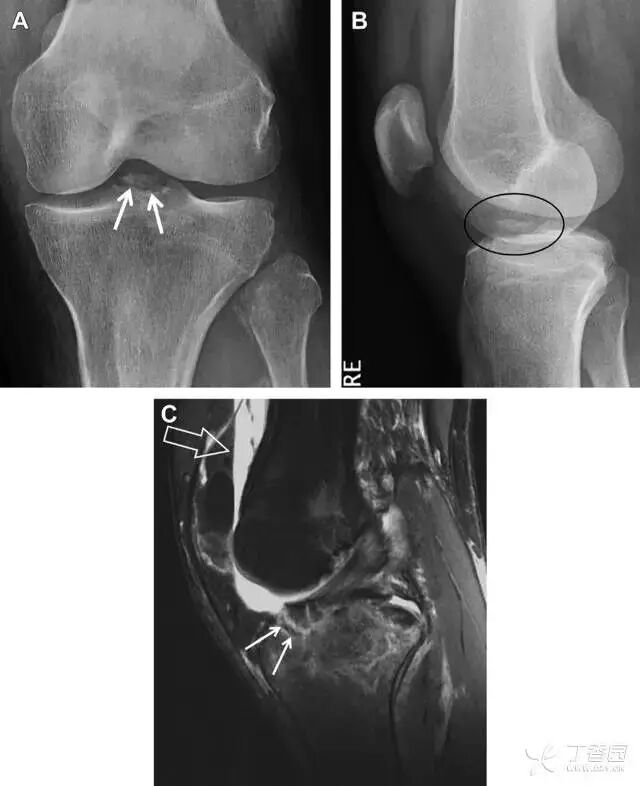

08前交叉韧带胫骨髁间嵴撕脱骨折

图 1 摩托车事故患者前交叉韧带撕脱性骨折

A 正位片示胫骨髁间嵴底部骨折(箭头),注意别把这个骨折碎片错认为关节内结构。B 侧位片示胫骨上方可见一细长型骨折碎片(椭圆)。C MRI 矢状位 T2 加权像示前交叉韧带附着于撕脱的骨折碎片上(箭头),注意周围存在骨髓水肿和积脂血征(空箭头)。